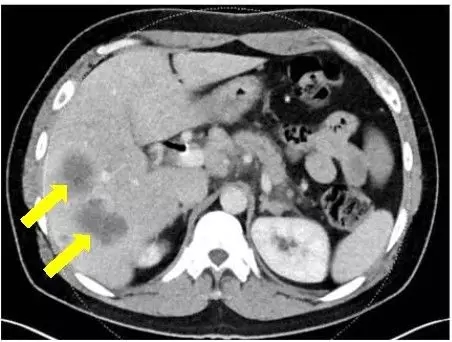

确诊时

在接受最强的化疗方案FOLFIRINOX后,肿瘤虽然缩小,但是他无法承受强烈的副作用。他的主治医生,丹娜法伯癌症研究院的Kimmie Ng博士检测了Broman的肿瘤DNA的全部外显子序列,显示BRCA2基因的突变。他的医疗团队决定使用靶向Brac突变的药物,称为PARP抑制剂的olaparib(Lynparza) ,尽管这款药物当时仅获批用于卵巢癌。

在他使用奥拉帕尼六个月后,MRI和CT扫描显示没有癌症复发,生物标志物水平保持在正常范围。Ng说,只要癌症得到控制,他可以无限期地服用奥拉巴利,因为副作用很小。

FOLFIRINOX治疗5个月病灶明显缩小 vs olaparib治疗21个月病灶全部消失